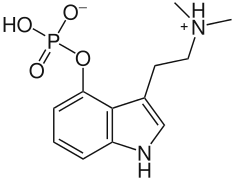

| Psilocybin | Fungi | 4-OPO3H2 | CH3 | CH3 | 4-phosphoryloxy-N,N-dimethyltryptamine | 520-52-5 |

| Aeruginascin | Fungi | 4-OPO3H2 | (CH3)3 | [3-[2-(trimethylazaniumyl)ethyl]-1H-indol-4-yl] hydrogen phosphate | 114264-95-8 | |